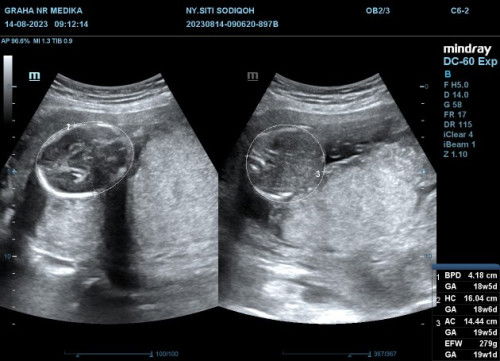

kehamilan 22minggu tp di hasil janin baru 19minggu . berarti bbjnya kurang bun ga sesuai . klo mau jelas usgnya 4d bun klo 2d ya emg bgitu hasilnya